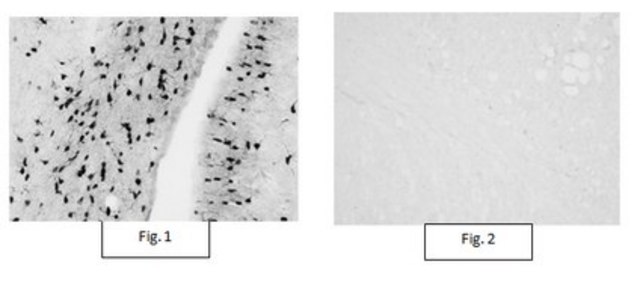

Immunohistochemistry Analysis: A representative lot detected Aspa/Nur7-positive oligodendrocytes in corpus callosum/external capsule using free-floating mouse brain sections (Courtesy of Dr. John R. Moffett, Uniformed Services University of the Health Sciences).